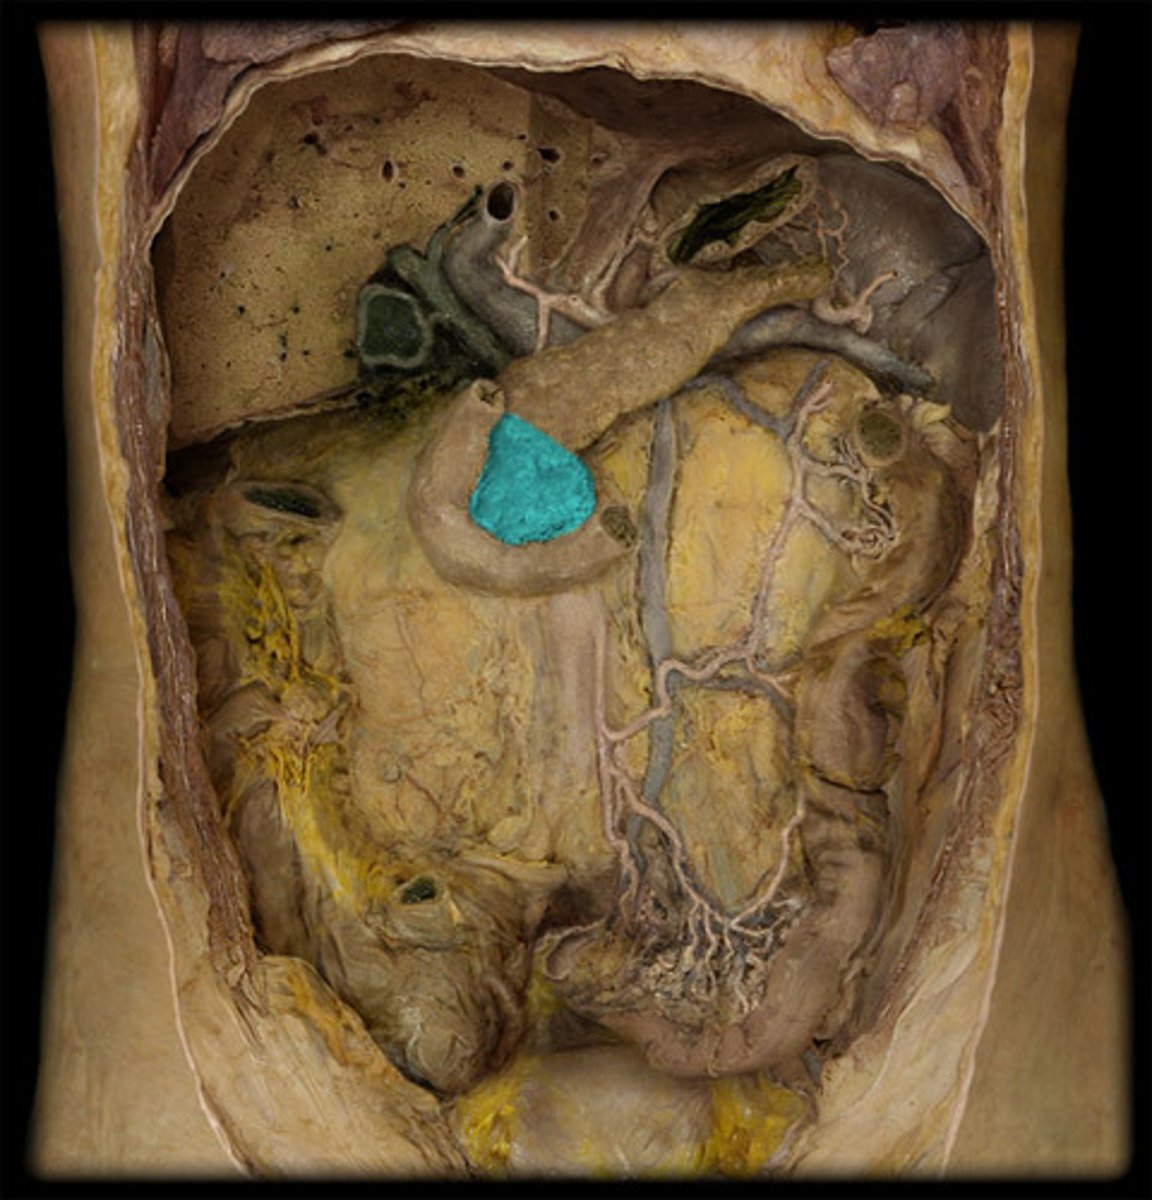

What is this?

Head of the pancreas

Body of the pancreas

Tail of the pancreas

Pancreatic duct

The bile duct and pancreatic duct form the...

Hepatopancreatic ampulla

The hepatopancreatic ampulla drains into the...

Ampulla of Vater